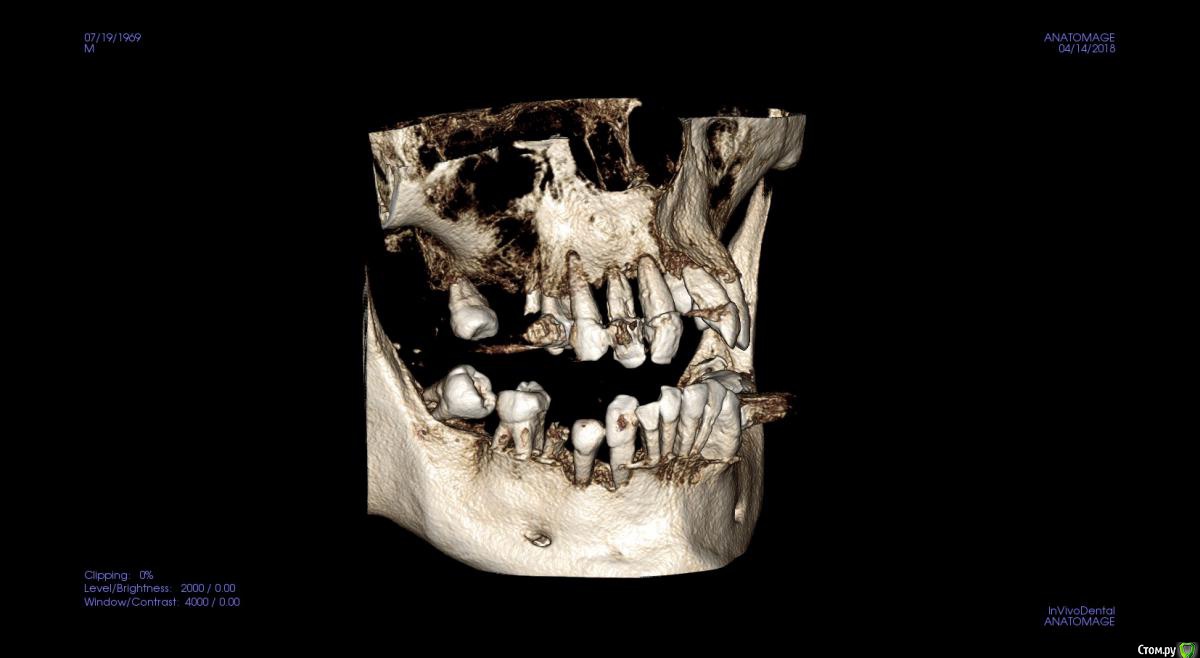

St. Опубликовано 17 апреля, 2018 Поделиться Опубликовано 17 апреля, 2018 Обзорные срезы ( верх, низ, топография нижнечелюстного нерва), дефект в обл 21 Ссылка на комментарий

kozloff Опубликовано 18 апреля, 2018 Поделиться Опубликовано 18 апреля, 2018 План действий.Удаление зубов.Повторное КТ.Рекомендуется костная пластика.Имплантация по шаблону. Ссылка на комментарий